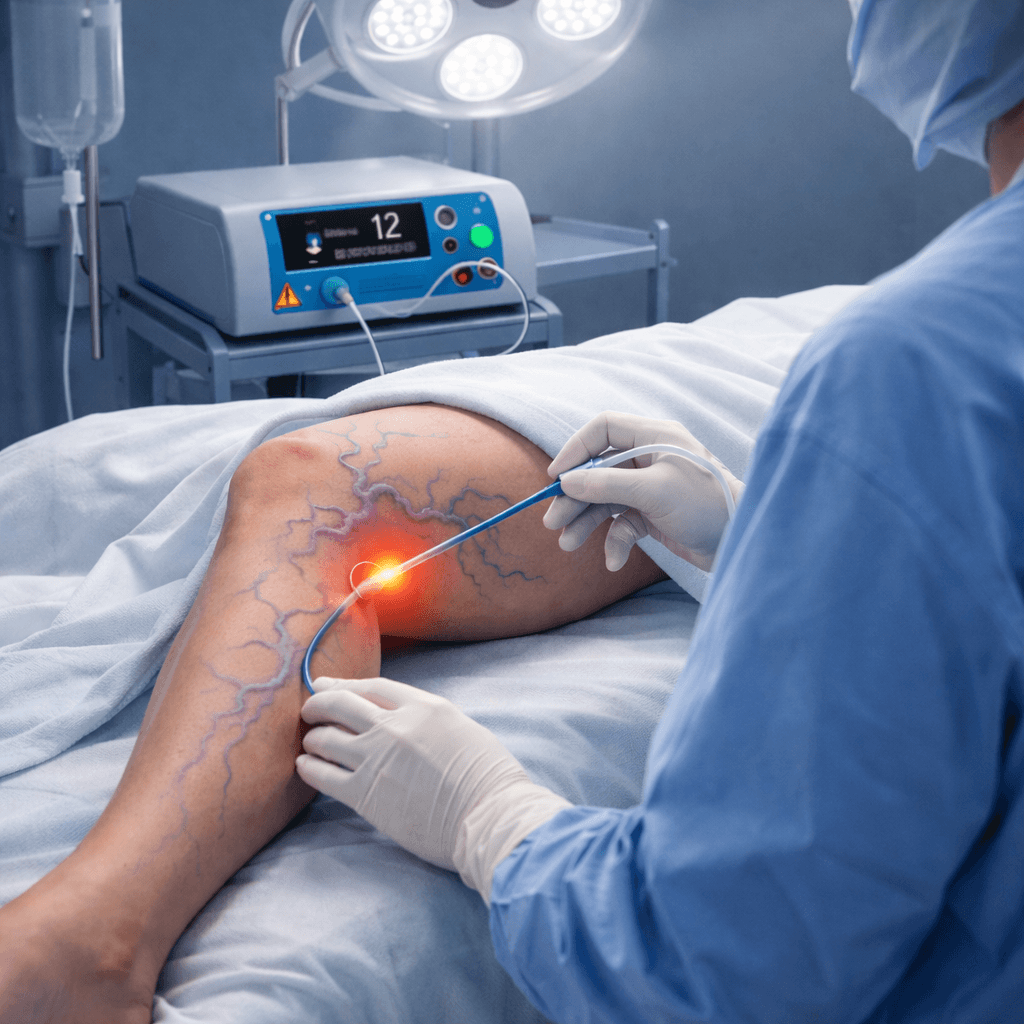

Robust Medical Diode Lasers, Fibres and Staplers

Our Product Applications

Minimally invasive procedures across multiple surgical specialities